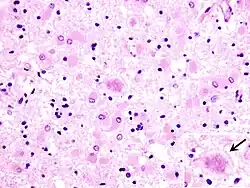

![]() Zmiany gąbczaste w obrazie mikroskopowym mózgu pacjenta z CJD | |

W badaniu neuropatologicznym w klasycznej postaci CJD stwierdza się triadę objawów:

- zmiany gąbczaste w neuropilu,

- ubytki neuronów,

- reakcję astrocytarną.

Zmiany o takim charakterze obecne są w różnych obszarach mózgowia. Zmiany gąbczaste są patognomoniczne dla całej grupy chorób, do której należy CJD. Niekiedy, w przypadkach o długim przebiegu, zmiany gąbczaste mogą zostać zamaskowane przez zaniki neuronów i astrocytarny rozplem gleju. Zmiany gąbczaste (ang. spongiform change) wymagają różnicowania ze stanem gąbczastym (spongiform state) pojawiającym się przy nasilonym uszkodzeniu kory. Astrocytozę można rozpoznać metodami impregnacyjnymi, takimi jak metoda Cajala albo Holzera. W korze mózgu glejoza włóknista zajmuje głębsze warstwy i towarzyszy zmianom gąbczastym, i dominują w niej formy gemistocytarne astrocytów. W korze móżdżku ma miejsce rozplem gleju Bergmanna i komórek Fañanása (lofogliocytów, gleju pióropuszowego). Niekiedy spotyka się nacieki zapalne wokółnaczyniowe o słabym nasileniu i prawdopodobnie niewielkim znaczeniu patogenetycznym.